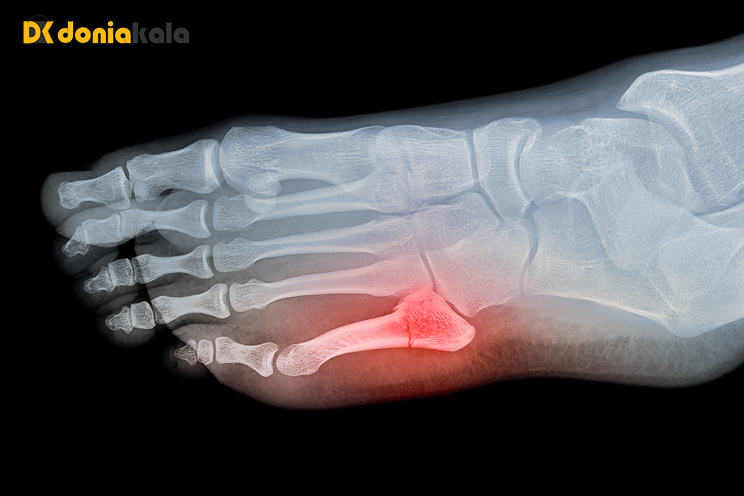

4. شکستگی انگشتان پا Fractures of the toes:

شکستگی انگشت پا یکی از شایع ترین شکستگی های اندام تحتانی است که توسط پزشک خانواده تشخیص داده می شود. شکستگی انگشتان پا اغلب در اثر آسیب له شدن یا نیروی محوری مانند ضربه زدن به انگشت پا ایجاد می شود.